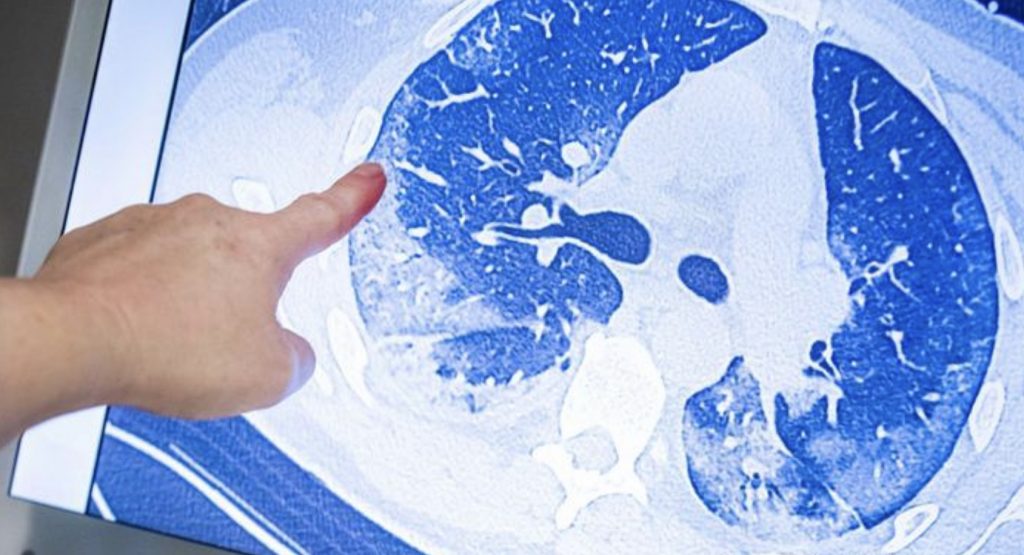

Sonuçları The Lancet tıp dergisinde yayımlanan bir araştırma, koronavirüsün uzun dönemli etkilerine dair yeni sonuçlar ortaya koydu. Koronavirüs pandemisinin patlak verdiği Çin’in Vuhan kentindeki hastaların verilerinin değerlendirildiği araştırmaya göre, 2020 yılının Ocak-Mayıs ayları arasında koronavirüse bağlı Covid-19 hastalığı nedeniyle tedavi gören kişilerin yüzde 76’sı hastalığın semptomlarından altı ay sonra dahi tamamen kurtulamadı.

Koronavirüsün uzun dönemli etkileri hakkındaki az sayıdaki çalışmadan biri olan araştırmada, hastanede tedavi gören bin 655 kişi tedavilerinden aylar sonra bir kez daha sağlık kontrolünden geçirildi. Bin 265 kişi en az bir şikayetinin devam ettiğini belirtti. En çok dile getirilen sağlık sorunu yorgunluk ve kas zayıflığı olurken, bazı hastalar uyku sorunları yaşadığını ifade etti.